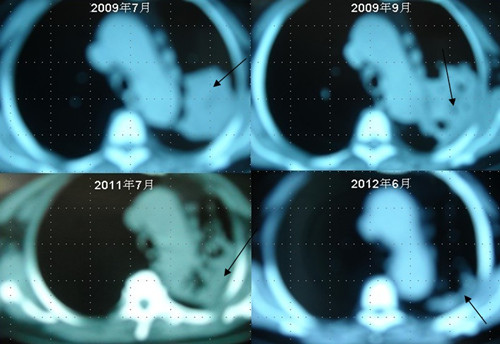

[提要] 患者李某某,女,64歲,于2009年6月因咳嗽、喘憋、痰中帶血,經(jīng)CT及病理等相關(guān)檢查確診為右肺上葉粘液腺癌, 縱膈淋巴結(jié)轉(zhuǎn)移, 左胸膜轉(zhuǎn)移,胸腔積液,因病情及體質(zhì)的原因無法接受手術(shù)及放化療等殺傷性治療,采用"中醫(yī)調(diào)胃、強腎、止血、化巖法"先后共治療8個月,現(xiàn)患者已有質(zhì)量的存活近3年。目前隨訪患者飲食、睡眠、體力均好,可獨立完成日常家務(wù),如今患者已經(jīng)67歲。肺癌病人李XX的病理圖片肺癌病人李XX采用“董氏治癌法”治療前后CT變化

肺癌病人李XX采用“董氏治癌法”治療前后CT變化